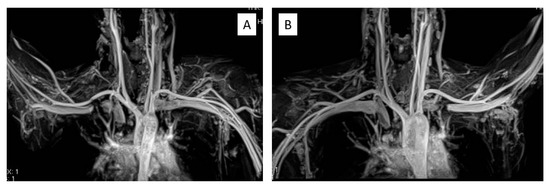

Representative Case